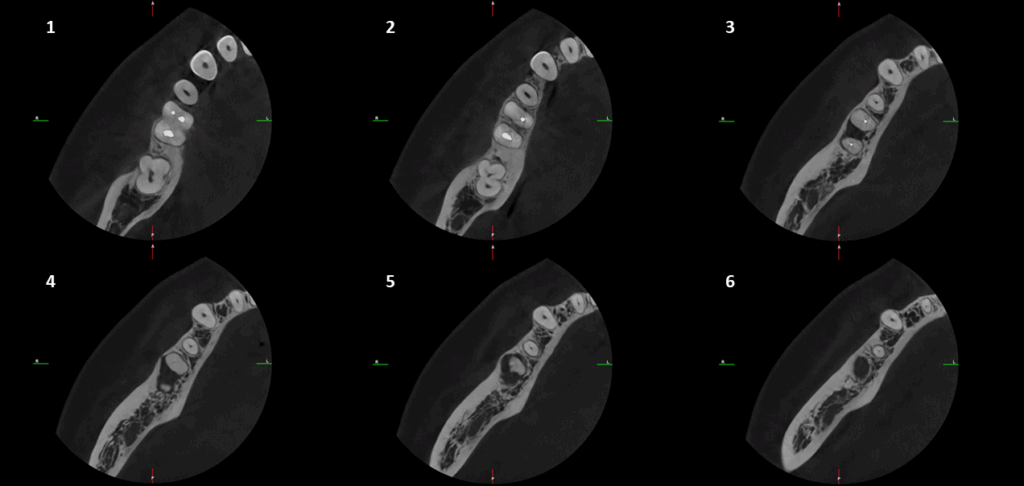

CORTES AXIALES